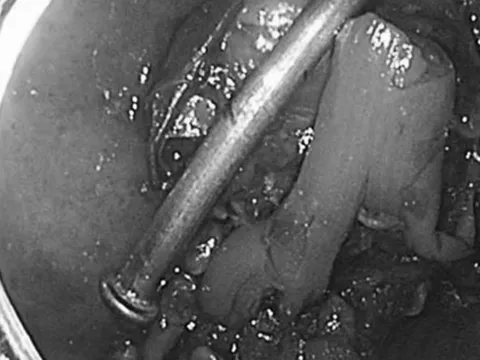

Ảnh minh họa.